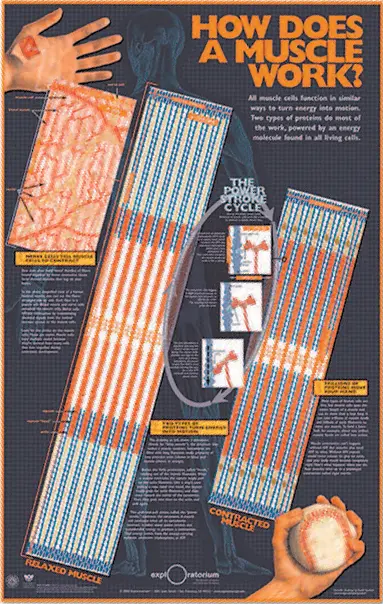

Инфографика «Как работают мышцы» Credit: Mark McGowan and David Goodsell, Exploratorium in San Francisco, California